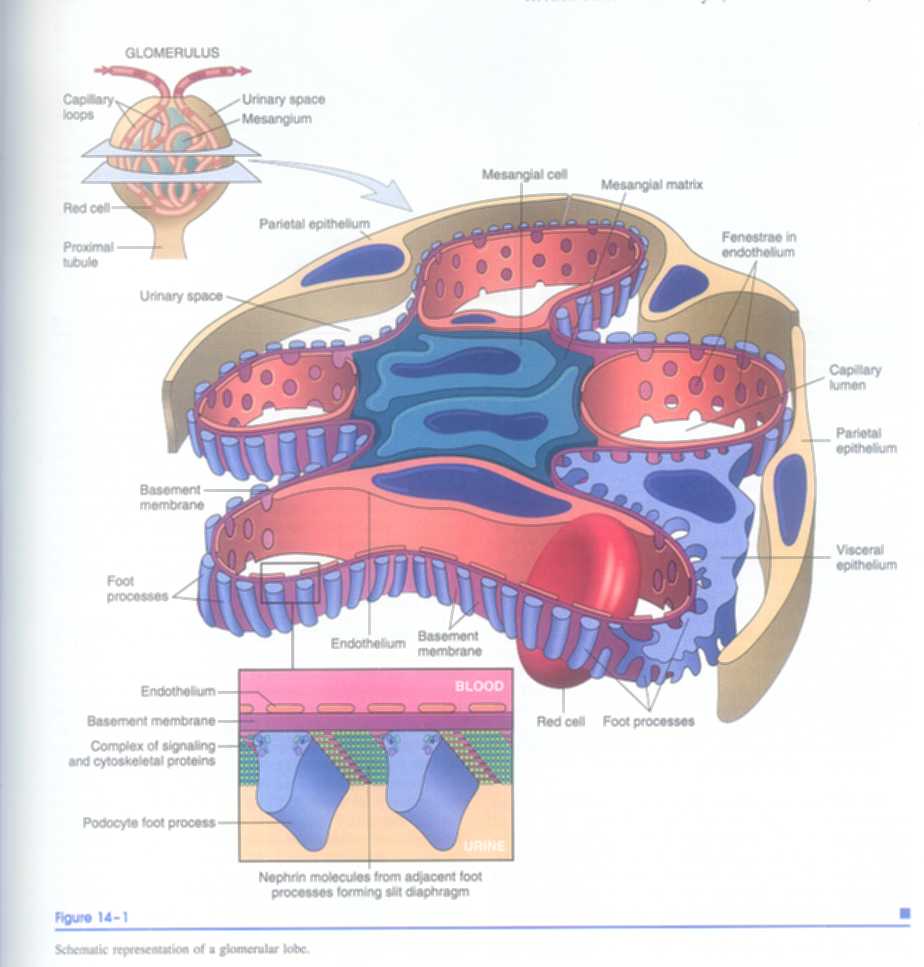

8 泌尿系统疾病

8.4 素材资源